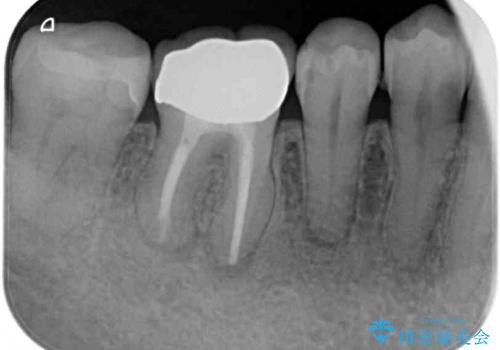

- 下顎の奥歯に頻繁に物が挟まるとのことで来院された患者様です。

最近ものが挟まりやすくなったり、冷たいものがしみるようになったりといった症状があり、診査したところ、歯質の欠損や不適修復物などが認められました。

精度の高いセラミックインレーによる修復治療を行うこととしました。